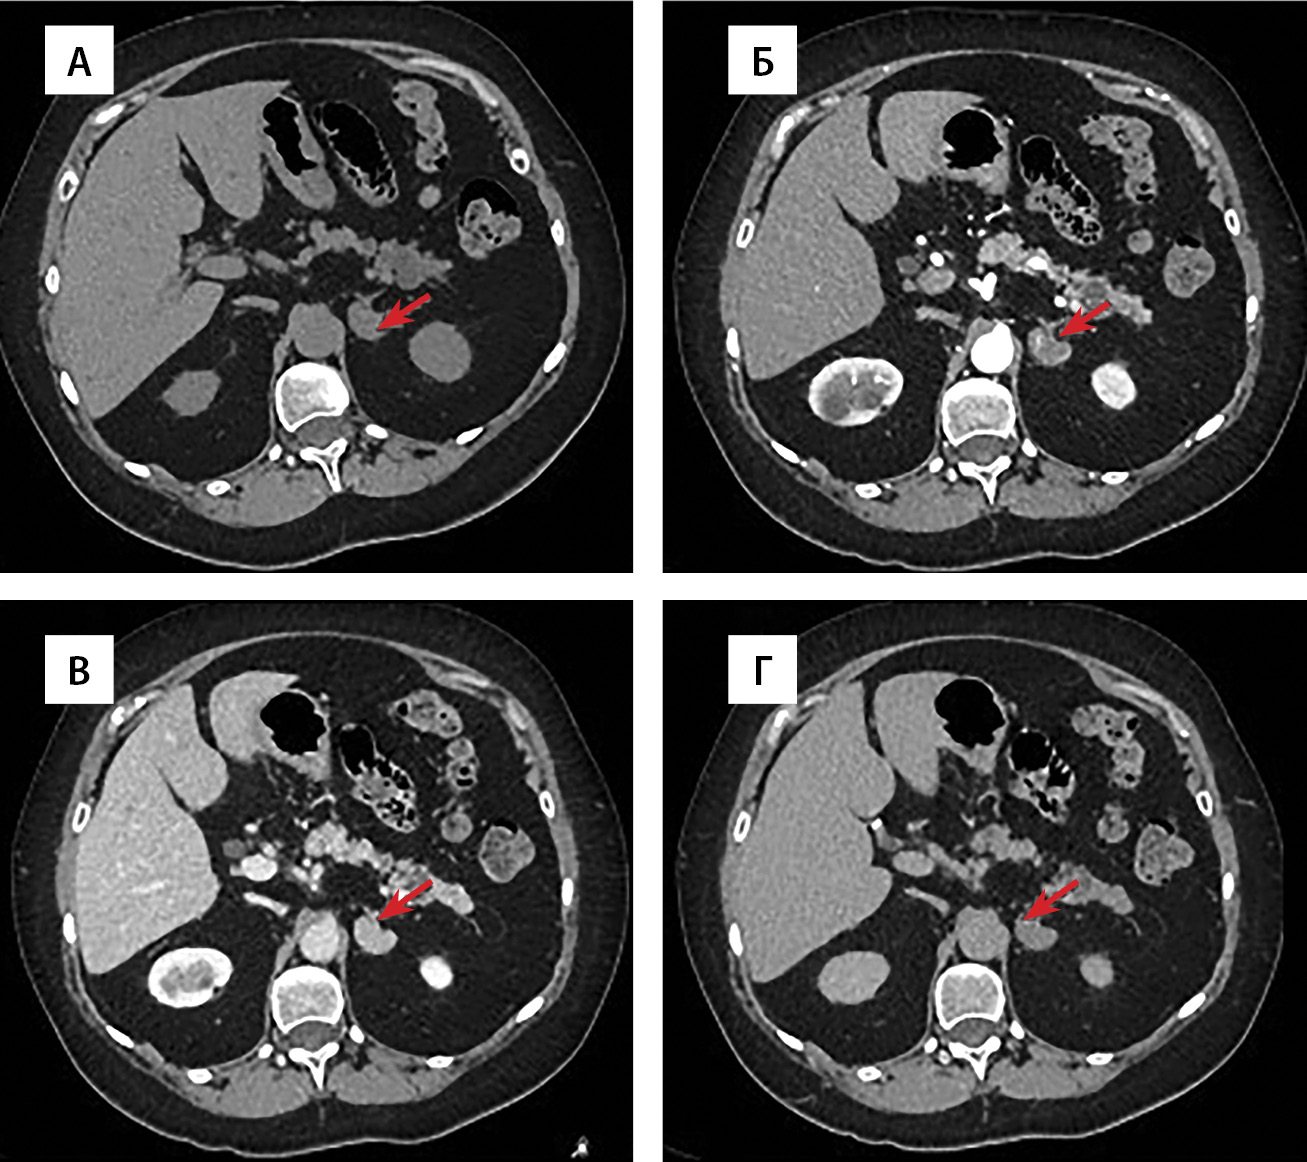

По данным мультиспиральной компьютерной томографии (МСКТ) надпочечников: образование левого надпочечника бобовидной формы с четкими ровными контурами, однородной структуры, размерами 25×14×20 мм. При болюсном контрастном усилении образование неоднородно накапливает контрастный препарат, максимально в венозную фазу. Плотность его по фазам составляет (нативная-артериальная-портальная-отсроченная): 50–59–106–54 ед.Н. Вымывание контрастного препарата: абсолютное 92,9%, относительное — 49,1%. Регионарные лимфатические узлы не увеличены. Образование правого надпочечника овальной формы с четкими бугристыми контурами, неоднородной структуры, размерами 29×41×35 мм. В структуре определяются кальцинаты. При болюсном контрастном усилении образование неоднородно накапливает контрастный препарат, максимально в венозную фазу. Плотность по фазам составляет (нативная-артериальная-портальная-отсроченная): 46–55–104–52 ед.Н. Вымывание контрастного препарата: абсолютное 89,7%, относительное — 50%. В артериальную фазу в структуре обоих образований определяются мелкие гиперконтрастные включения плотностью до 188 ед.Н. Регионарные лимфатические узлы не увеличены (рис. 1, 2, 3). По заключению — образования обоих надпочечников необходимо дифференцировать между атипичными аденомами с низким содержанием жира и образованиями злокачественной природы.

Рисунок 1. Мультиспиральная компьютерная томография образования левого надпочечника, аксиальная проекция: А — нативная фаза; Б — артериальная фаза; В — портальная фаза; Г — отсроченная фаза.

3. Рисунок 1. Мультиспиральная компьютерная томография образования левого надпочечника, аксиальная проекция: А — нативная фаза; Б — артериальная фаза; В — портальная фаза; Г — отсроченная фаза. | |

МСКТ надпочечников является методом выбора для их визуализации, так как помогает определить размер, структуру, контуры и нативную плотность выявленного образования, а также оценить характер его контрастирования. Ключевыми дифференциально-диагностическими признаками аденом с низким содержанием жира являются: высокая нативная плотность (>10 ед.Н.), однородное накопление контрастного препарата в фазы контрастного усиления (преимущественно в портальную) и выраженное его вымывание к отсроченной фазе (на 15-й минуте исследования) [22]. В свою очередь, злокачественный потенциал можно заподозрить при неоднородности структуры образования, в том числе в фазы болюсного контрастного усиления, а также при задержке вымывания контрастного препарата в отсроченную фазу (абсолютный процент вымывания <60% или относительный <40%) [23, 24]. По результатам последних исследований было выявлено, что аденомы с низким содержанием жира в большинстве случаев (более 75% случаев) представляют собой онкоцитомы, при этом около 1/3 из них имеют пограничный потенциал злокачественности [25]. В настоящее время, к сожалению, не существует достоверных КТ-критериев дифференциальной диагностики доброкачественных онкоцитарных опухолей от образований с пограничным и злокачественным потенциалом [26]. В нашем наблюдении заподозрить онкоцитому, в том числе со злокачественным потенциалом, можно ввиду наличия нетипичного для аденомы неоднородного накопления контрастного препарата в артериальную фазу, где определялись мелкие гиперконтрастные участки. Таким образом, в дальнейшем при выявлении у аденомы с низким содержанием жира атипичных КТ-признаков, например, неоднородности контрастирования, целесообразно включать онкоцитарную опухоль в дифференциальную диагностику.